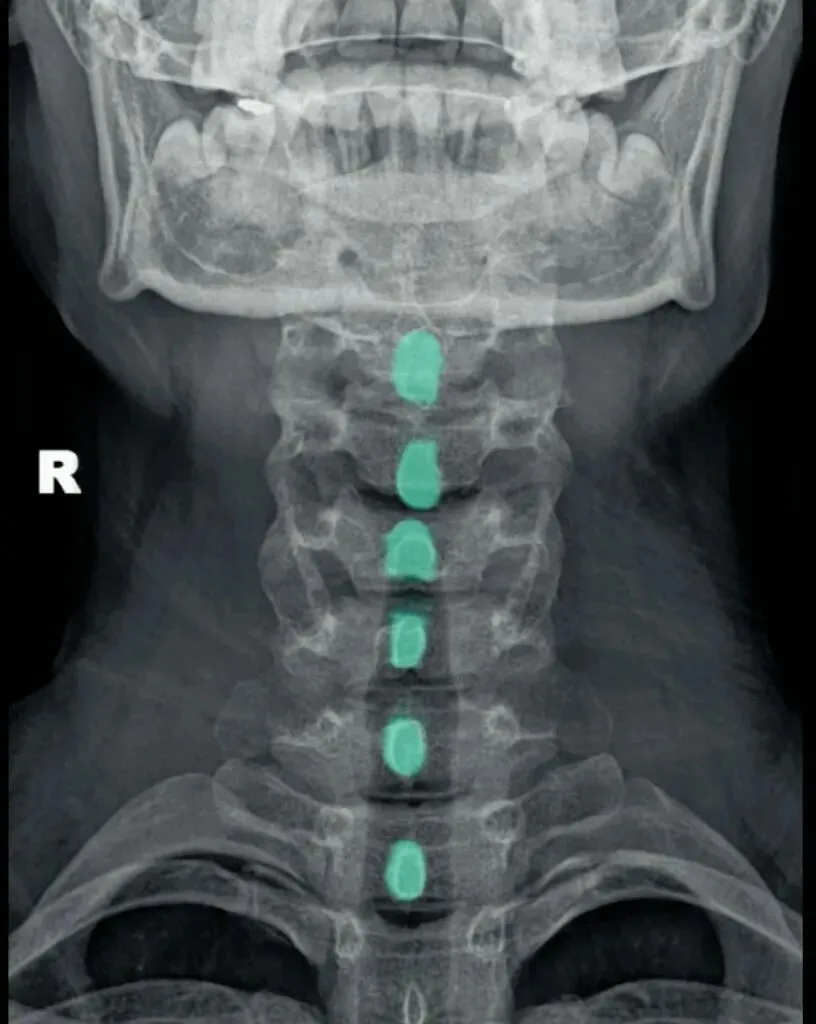

六旋指颈椎旋转,需结合颈椎正侧位观察。

颈椎正位主要观察棘突有没有偏歪,有没有在棘突中心轴线的连线上。

如果某一节椎骨的棘突中心点偏离,各棘突中心连线大于等于3毫米,则表示该节段颈椎有轴向旋转。

侧位主要观察椎体有没有双边征和关节突有没有双突征。

造成这两个征象的原因就是椎体后缘及双侧关节突没有完全重叠,摄影体位不标准时也会出现这种现象。所以我们要结合正侧位观察,如果正位没有出现某节段颈椎棘突偏移,但是侧位出现颈椎双凸或双边征时,大概率就是摄影体位不标准。反之正位能看到某节段颈椎棘突偏移,同时侧位能看到对应节段颈椎的双边或者双凸征时,基本可以确定椎体存在旋转。